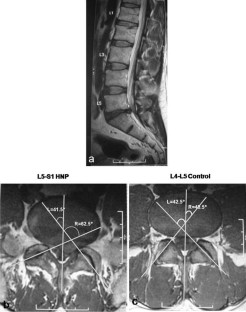

Sixty patients (18–40 years) with single level disc herniation (L3–L4, L4–L5, or L5–S1) were included in the study. Facet angles were measured using MRI of 3-T using the method described by Karacan et al. Facet tropism was defined as difference of 10° in facet joint angles between right and left sides. Normal disc adjacent to the herniated level was used as control. We also examined if disc herniated towards the side of more coronally oriented facet.

Twenty-five herniations were at L4–L5 level and 35 at L5–S1. Statistical analysis was performed using the Fischer Exact Test. At L4–L5 level, 6/25 cases had tropism compared to 3/35 controls (p = 0.145). At L5–S1 level, 13/35 cases had tropism as compared to 1/21 controls (p = 0.0094). Of 19 cases having tropism, the disc had herniated towards the coronally oriented facet in six (p = 0.11).

Fig. 2

Fig. 3